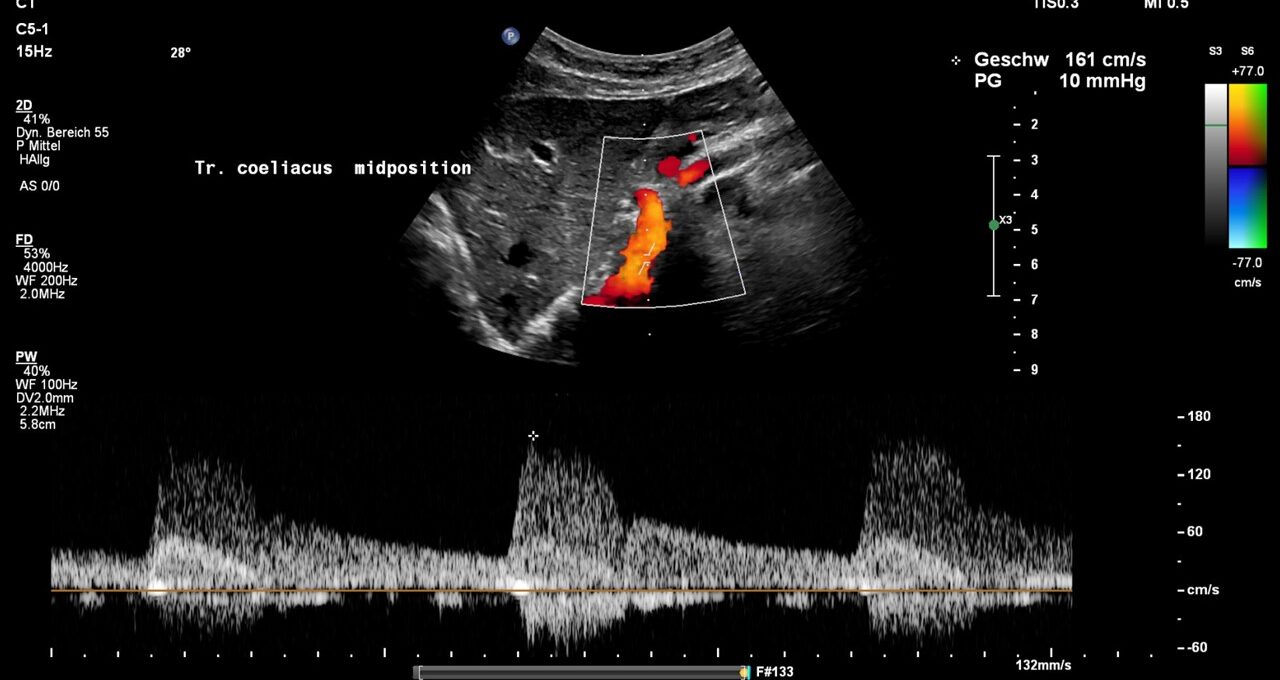

The systolic flow velocity in the abdominal aorta is only 80 cm/s. This indicates the compliance of the aortic vessel wall. However, in the celiac trunk, there are significantly increased flow velocities that vary with breathing, namely 161 cm/s in the middle respiratory position, 287 cm/s during inspiration, and 210 cm/s during expiration. This indicates ligamentum arcuatum syndrome, whose typical symptoms are vegetative symptoms such as nausea, circulatory dysregulation, disturbed peristalsis, sudden skin redness, and loss of appetite, as well as, of course, severe postprandial epigastric abdominal pain—the patient’s main symptom.